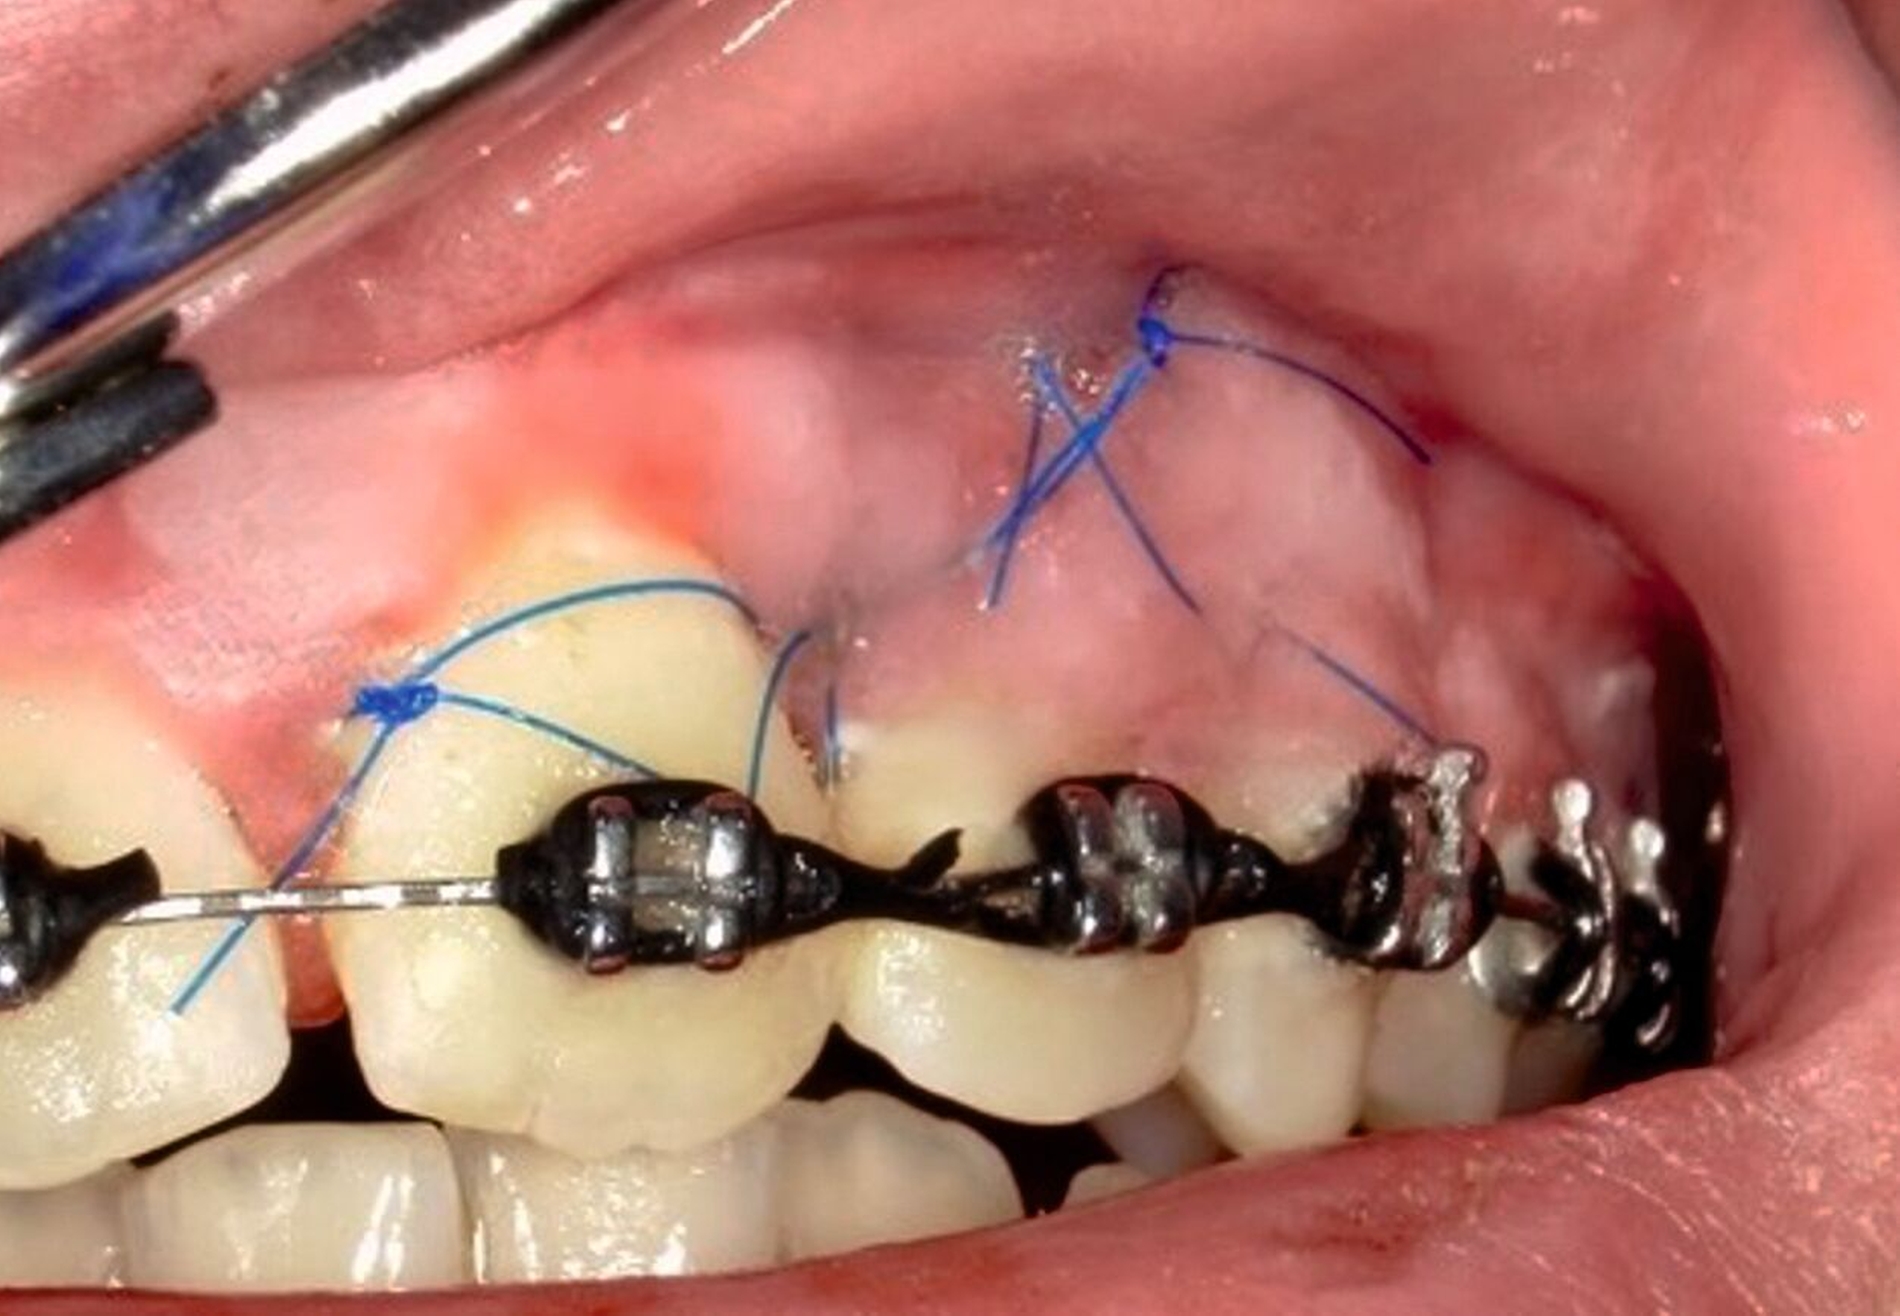

Die Pulpenvitalität der angrenzenden Zähne 21 und 22 war erhalten. Basierend auf der Anamnese, dem klinischen Befund und dem radiologischen Bild wurde die Verdachtsdiagnose eines benignen odontogenen Tumors gestellt. Als Therapie der Wahl erfolgte die Enukleation des Befundes in toto unter Lokalanästhesie. Nach Mobilisation des Mukoperiostlappens wurde ein Weichgewebssack sichtbar. Die Tumorkapsel war fest am intraalveolären Knochen fixiert (Abbildung 3).

Die entstandene ossäre Kavität wurde mit einem Knochenersatzmaterial mit Kollagenzusatz aufgefüllt, und es wurde ein plastischer Wundverschluss durchgeführt (Abbildung 4). Das entnommene Gewebe wurde zur histopathologischen Untersuchung in die Pathologie der Universitätsmedizin Mainz eingesandt. Histologisch zeigte sich ein zellarmes, bindegewebiges Stroma mit strangförmig angeordneten Zellen odontogenen Epithels.